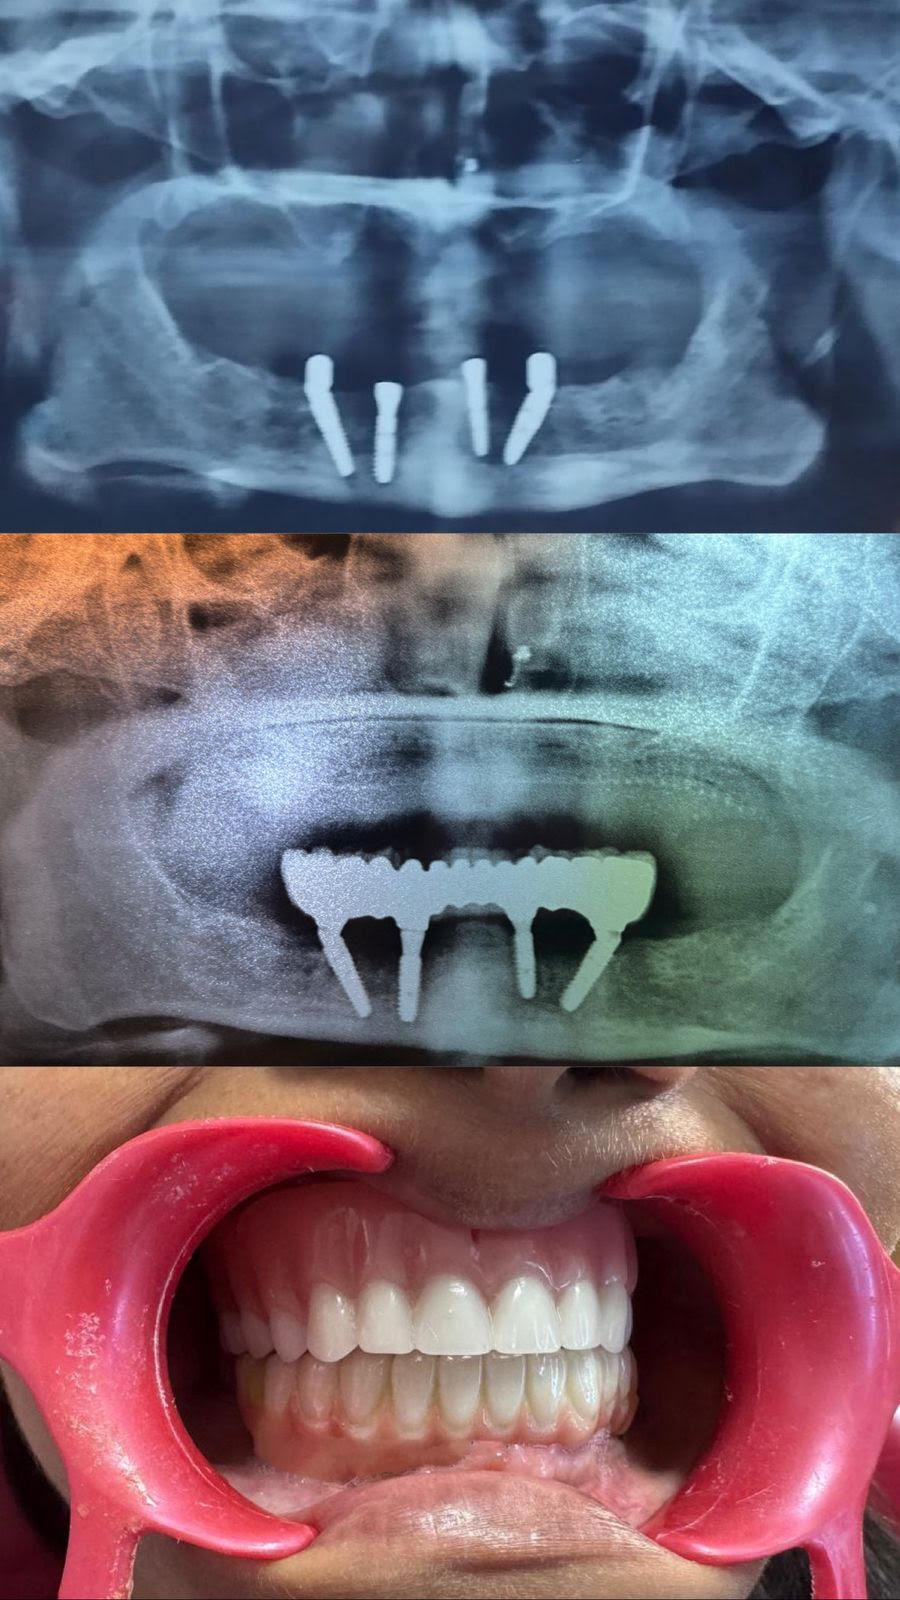

Dental implants are artificial tooth roots made from biocompatible titanium, surgically placed into your jawbone. They act as a strong, permanent foundation for fixed or removable replacement teeth, designed to look, feel and function just like your natural teeth.

A titanium post is gently placed into your jawbone under local anesthesia.

The implant naturally fuses with the bone through a process called osseointegration.

A custom-made crown is securely attached to restore your tooth’s full function and aesthetics.